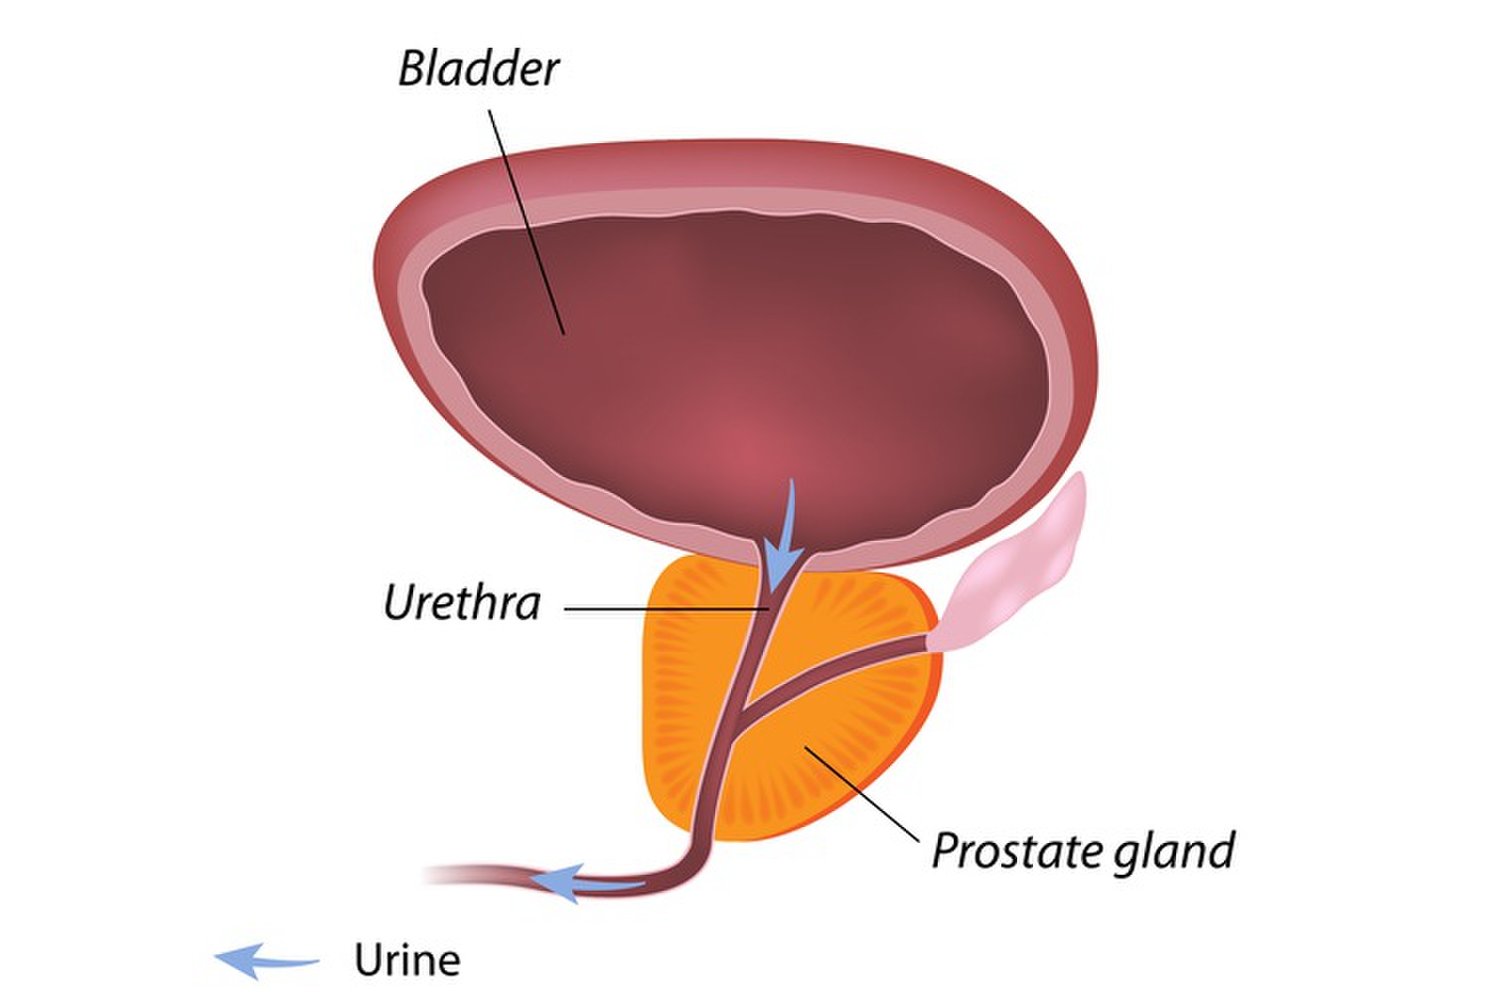

Простата, обычно ассоциируемая с мужским здоровьем после полового созревания, также присутствует у детей, хотя и в значительно меньших размерах. Этот орган, расположенный под мочевым пузырем и окружающий уретру, играет роль в выработке жидкости, которая составляет часть семенной жидкости. Несмотря на то, что проблемы с простатой у детей встречаются редко, понимание её развития и потенциальных патологий важно для ранней диагностики и лечения.